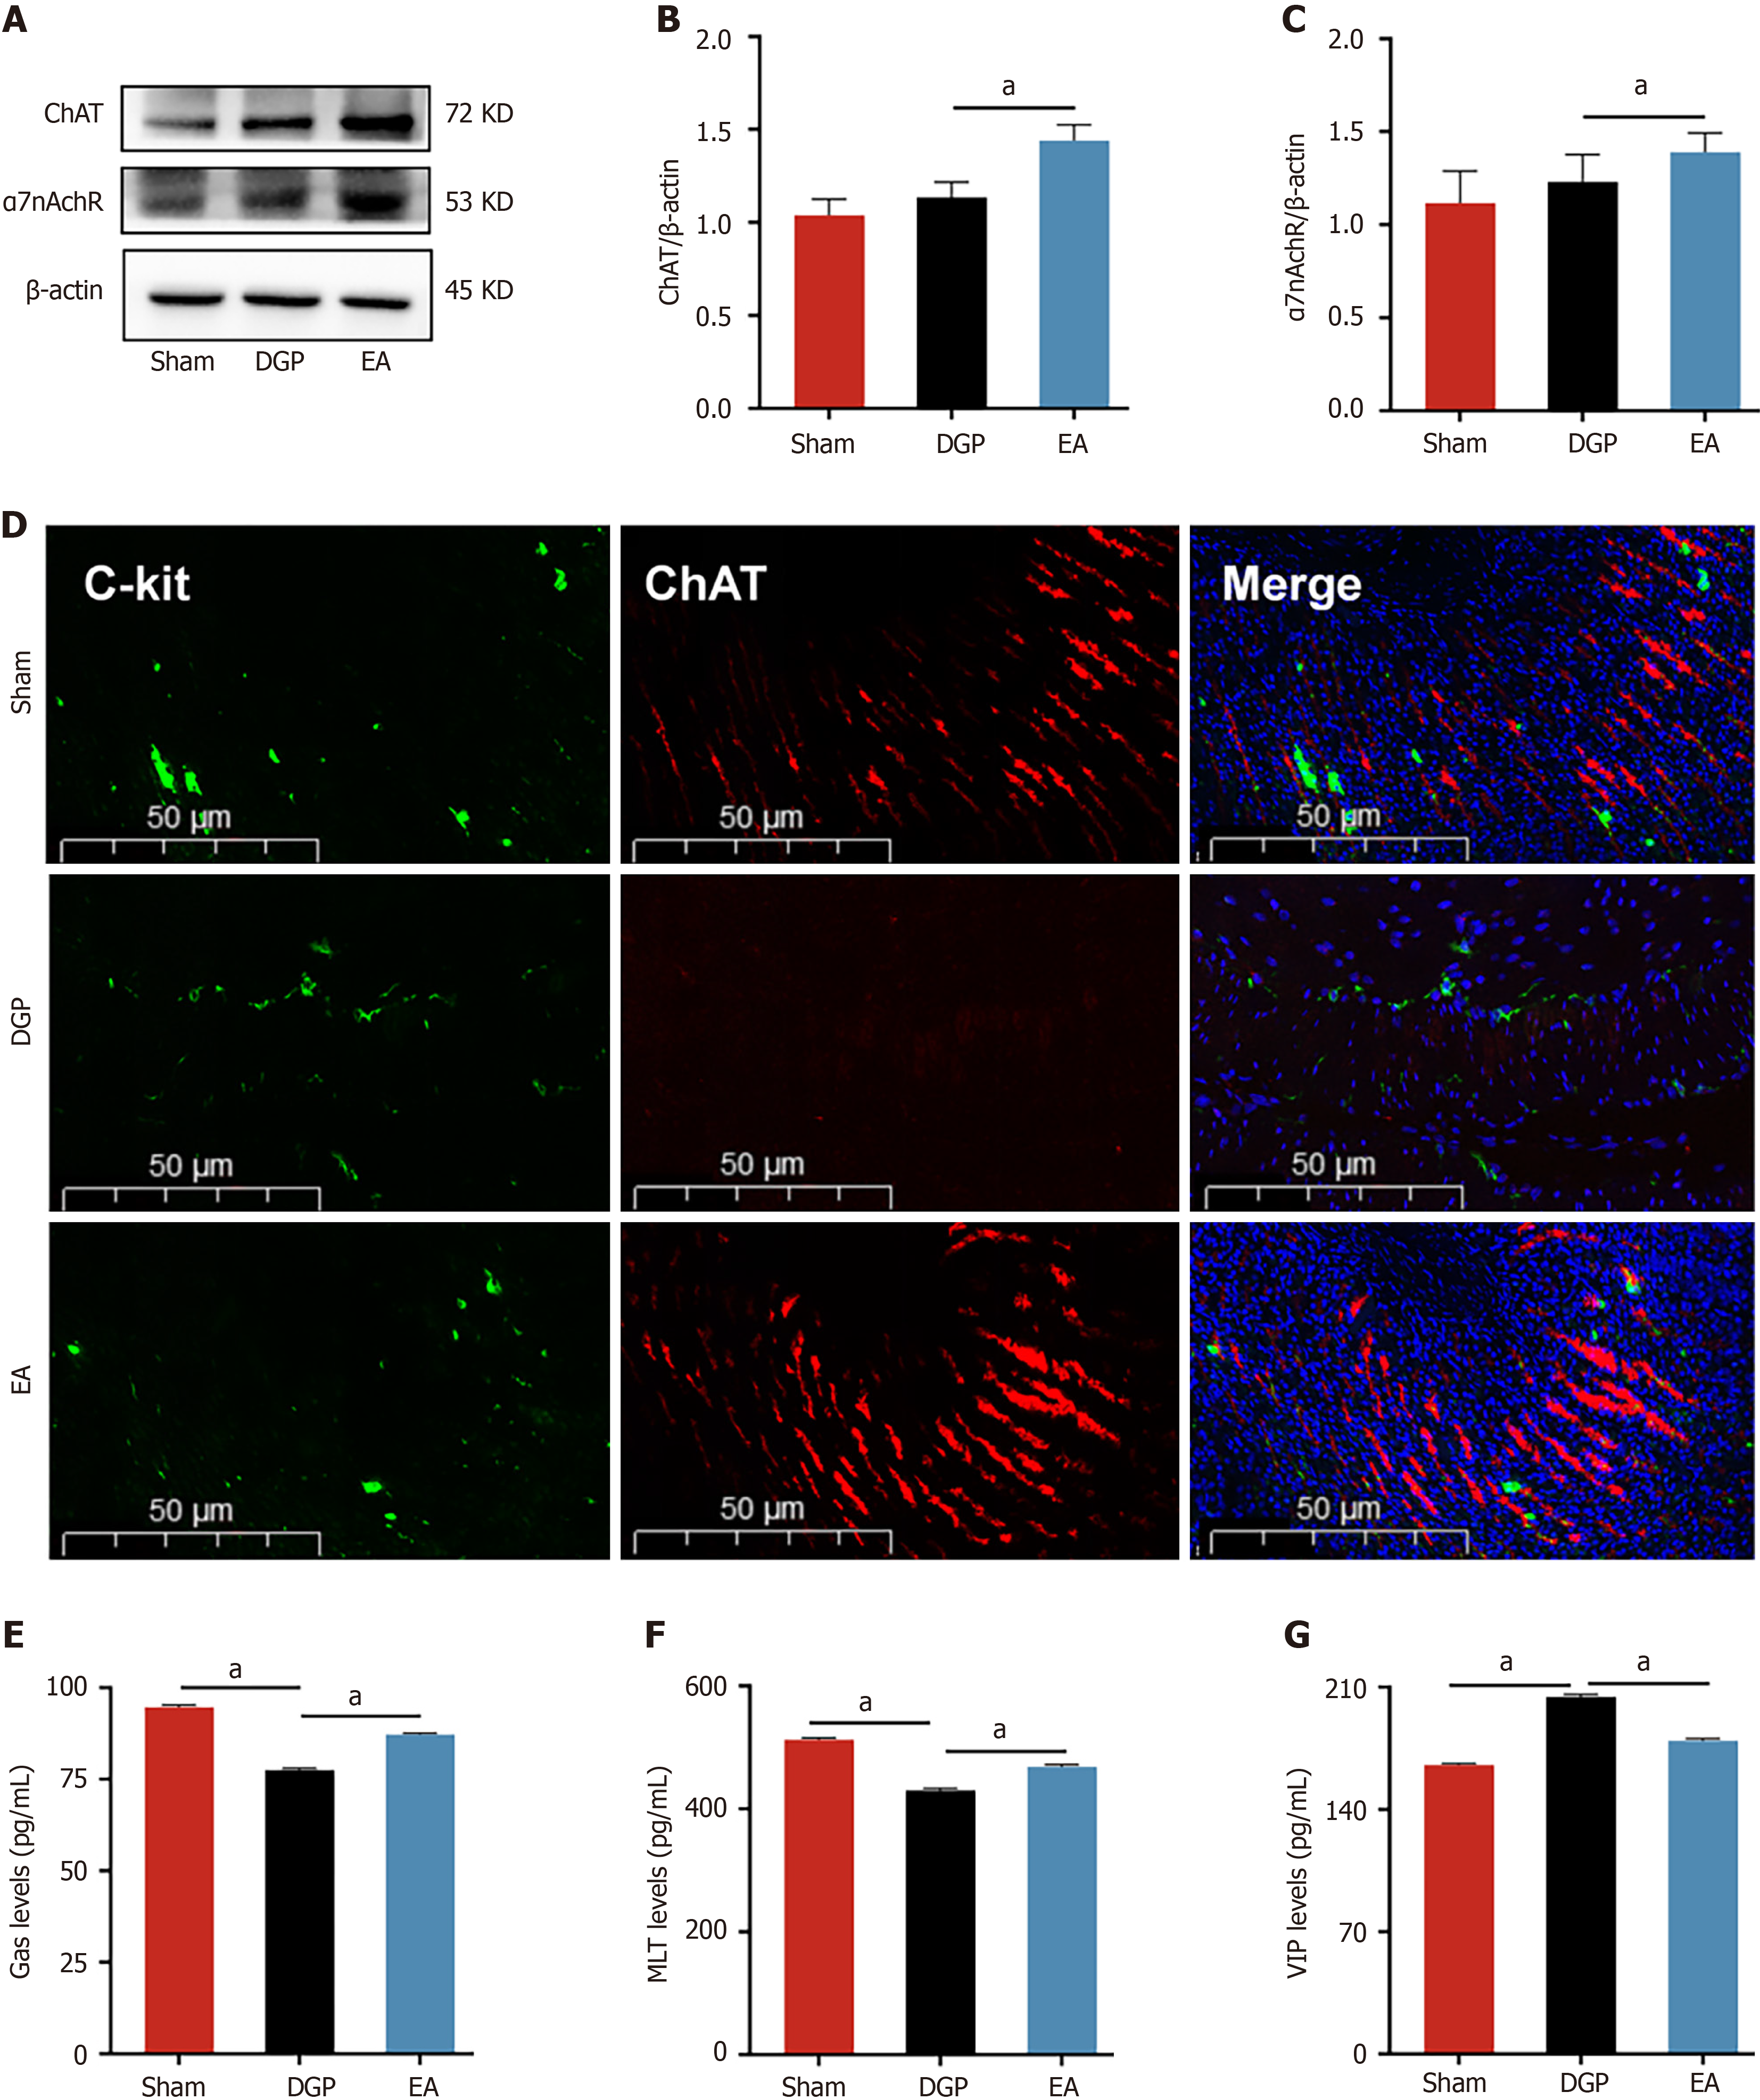

The vagus nerve is the principal neural regulator of gastrointestinal motility. In order to elucidate its role in EA-mediated improvements, a comprehensive analysis was conducted on key vagal targets in gastric tissues. The results of the immunoblot analysis revealed that EA induced upregulation of the cholinergic markers ChAT and α7nAchR in comparison with DGP controls (P < 0.05, Figure 3A-C). Furthermore, immunofluorescence co-localization analysis demonstrated parallel restoration of C-kit +/ChAT + expression patterns, with EA-treated rats showing distribution characteristics comparable to the Sham group (Figure 3D). This suggests that the vagus nerve target ChAT may be involved in the regulatory effect of EA on ICC. Assessment of gastrointestinal peptides further revealed characteristic alterations. Compared with the Sham group, DGP rats exhibited significant suppression of stimulatory mediators (Gas and MLT), accompanied by a concomitant paradoxical elevation in inhibitory VIP levels (P < 0.05). However, the EA intervention led to the normalization of these peptide profiles, with a significant increase in Gas and MLT levels (P < 0.05) and a reduction in VIP levels (P < 0.05) (Figure 3E-G). The EA intervention appears to have restored gastric motility in DGP rats by coordinating the activation of the vagal cholinergic pathway to regulate ICC cells and rebalance neuroendocrine signals.